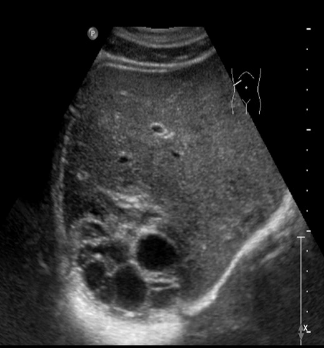

Identify this image.

Late stage echinococcal or Hydatid cyst